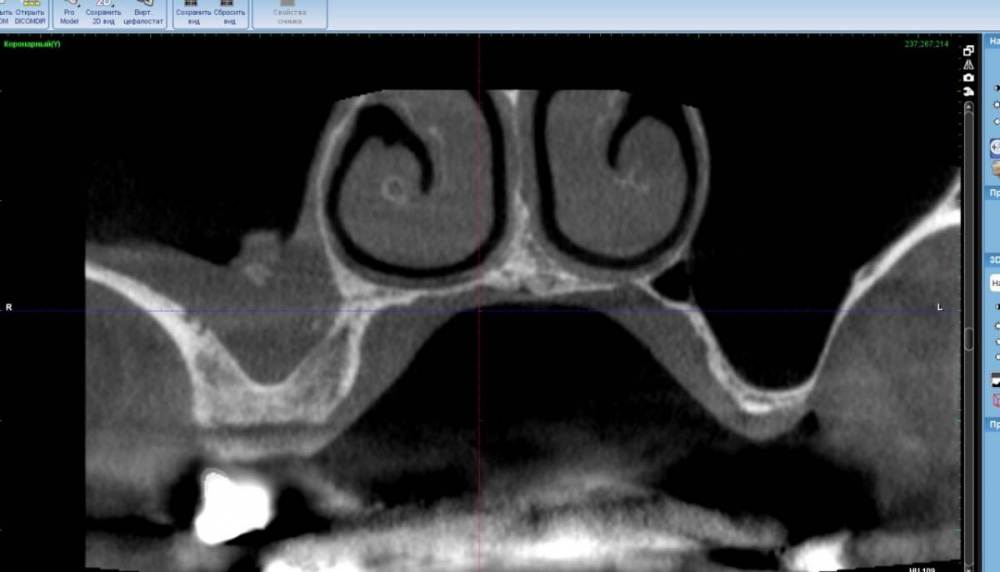

TIGER Опубликовано 22 сентября, 2022 Поделиться Опубликовано 22 сентября, 2022 (изменено) https://youtu.be/Flx36Opddh полное видео операции тут☝? Рутинный кейс)Закрытый синус,как всегда в скоп и при помощи пьезотома ,последнее фото результат через 6 месецев перед фиксацией протетики? Изменено 22 сентября, 2022 пользователем TIGER 5 1 Ссылка на комментарий

TIGER Опубликовано 7 октября, 2022 Автор Поделиться Опубликовано 7 октября, 2022 Финал 1 Ссылка на комментарий